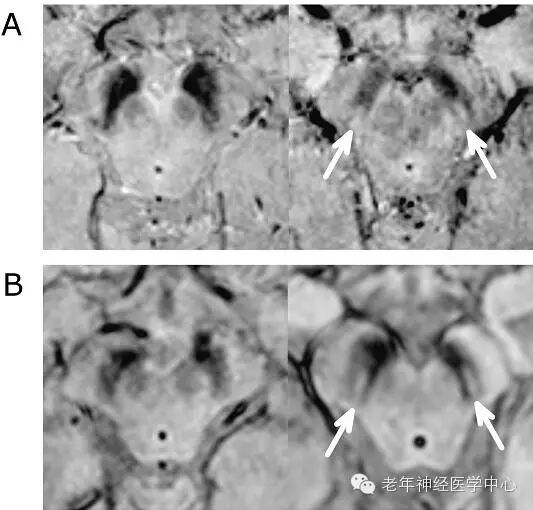

2013年,研究人员发现了一种新的帕金森病生物指标,称为Nigrosome,其不仅可用于诊断病情,同时也无形中追踪病情的发展。“The ‘Swallow Tail’ Appearance of the Healthy Nigrosome – A New Accurate Test of Parkinson’s Disease: A Case-Control and Retrospective Cross-Sectional MRI Study at 3T”描述了这种成像标志的缺席如何可以帮助诊断帕金森病。

利用高分辨率的超高场7T磁共振成像,诺丁汉研究小组已经找到了帕金森病的病理特点,在中脑一个小区域(黑质体substantia nigra)的结构变化。最新的研究表明,利用全国各地医院都有的3T磁共振成像技术也能检测这些变化。随后,他们创造了短语“燕尾状外观”作为健康黑质体的一种易于识别的标志,而黑质体在帕金森病中是缺失的。研究人员回顾了总共114个高分辨率扫描,在94%的例子中,利用这种技术能够做出精确诊断。

“使用磁共振成像(没有电离辐射,并且比核医学技术便宜很多),我们可以确定一种特殊的影像特征,它与燕子的尾巴形状非常相似,因此我们将其称为‘燕尾征’。在帕金森病中缺乏这种标志。”